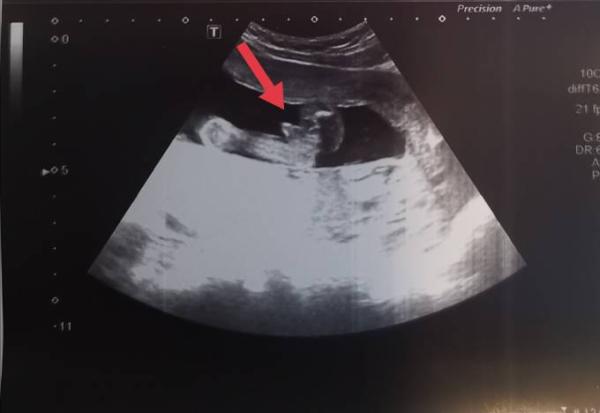

Ich tendiere auch zu Mädchen.. Bei uns sah das Jungen Outing in der 17 ssw deutlicher aus..

Bild zu

Okay das erkennt man wirklich deutlicher